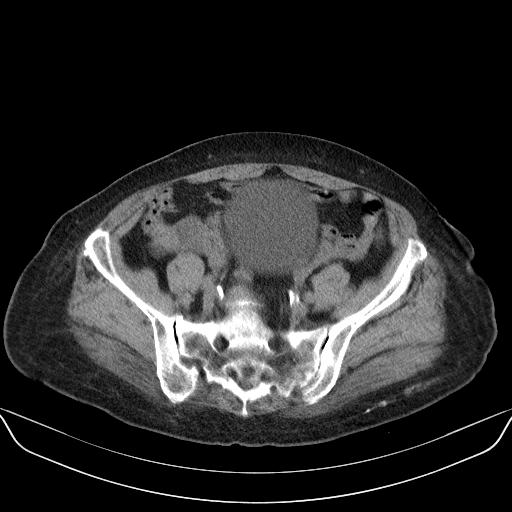

以下是引用yuhongjun在2010-3-12 6:32:00的发言:[br]回肠末端间质瘤,不除外阑尾粘液囊腺瘤,臀部注射性肉芽肿钙化. [br] [br]